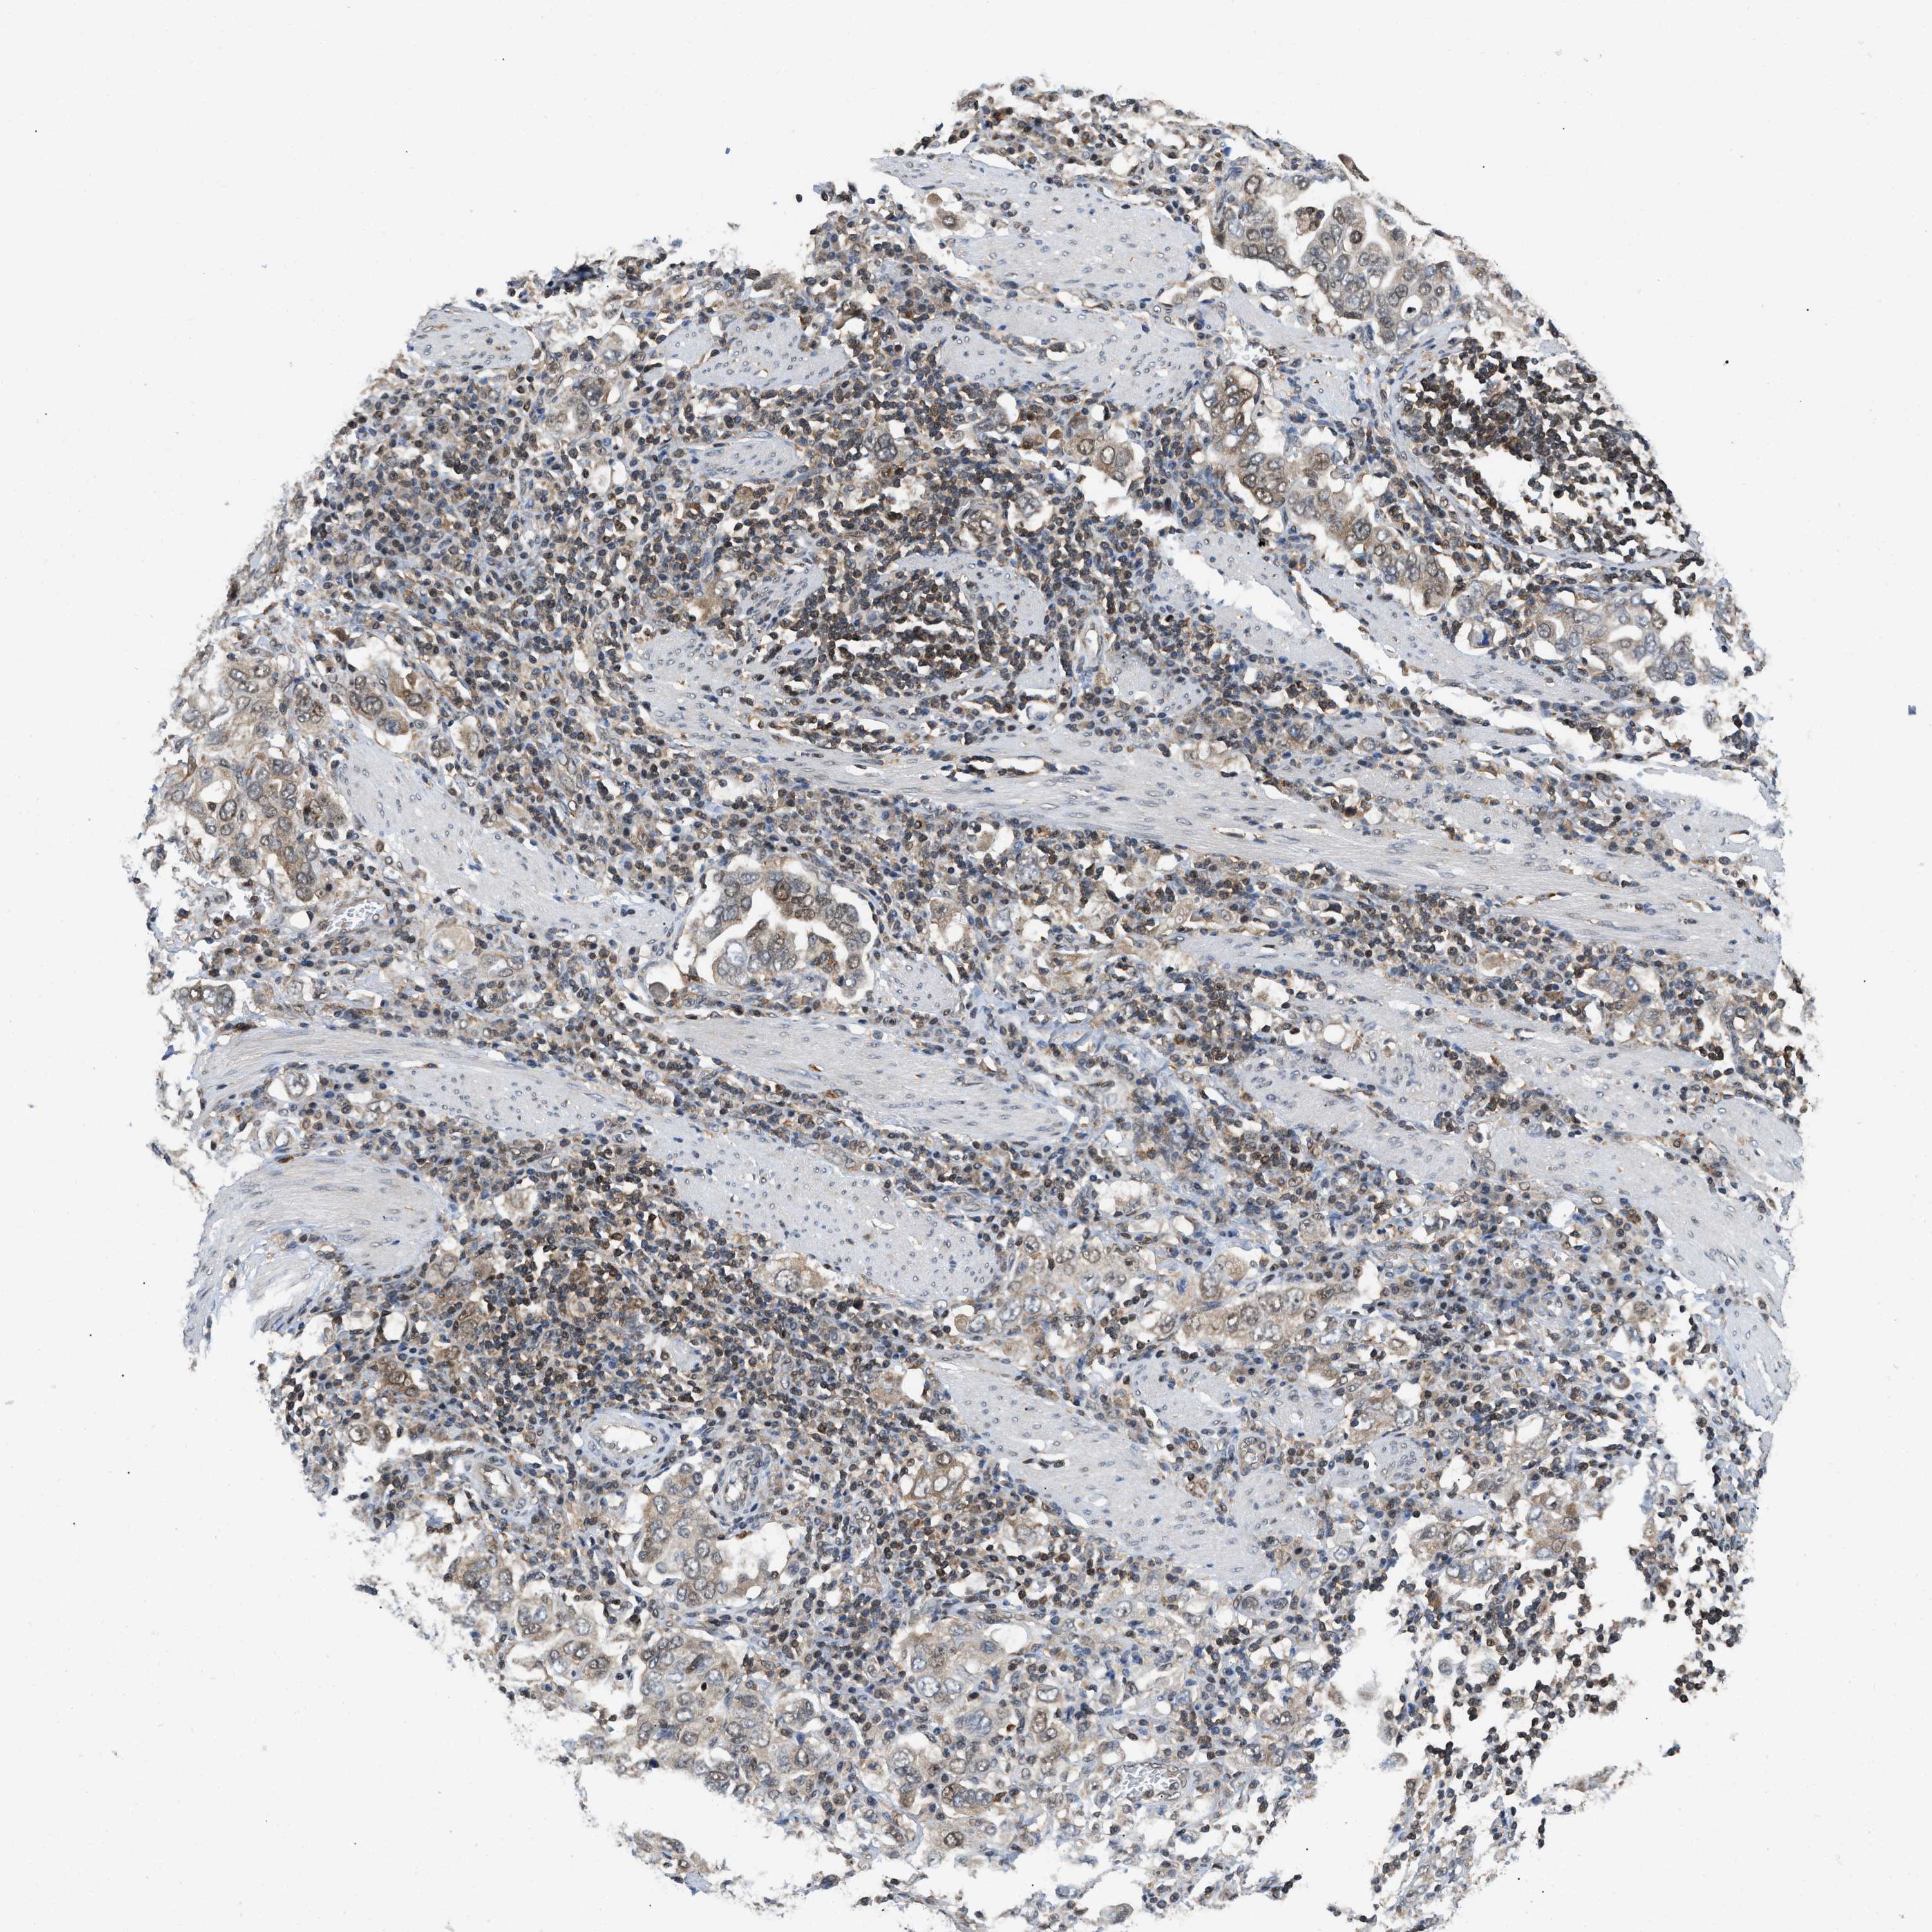

STOMACH CANCER - Protein expressioni

A mouse-over function shows sample information and annotation data. Click on an image to view it in a full screen mode. Samples can be filtered based on level of antibody staining by selecting one or several of the following categories: high, medium, low and not detected. The assay and annotation is described here.

Antibody stainingi

Antibody staining in the annotated cell types in the current human tissue is reported as not detected, low, medium, or high, based on conventional immunohistochemistry profiling in selected tissues. This score is based on the combination of the staining intensity and fraction of stained cells.

Each image is clickable and will lead to virtual microscopy that enables deeper exploration of all samples and also displays staining intensity scores, fraction scores and subcellular localization as well as patient and tissue information for each sample.

Antibody HPA016578

Antibody HPA023505

Staining

High

Medium

Low

Not detected

Intensity

Strong

Moderate

Weak

Negative

Quantity

>75%

75%-25%

<25%

None

Location

Nuclear

Cytoplasmic/membranous

Cytoplasmic/membranous,nuclear

Adenocarcinoma, NOS